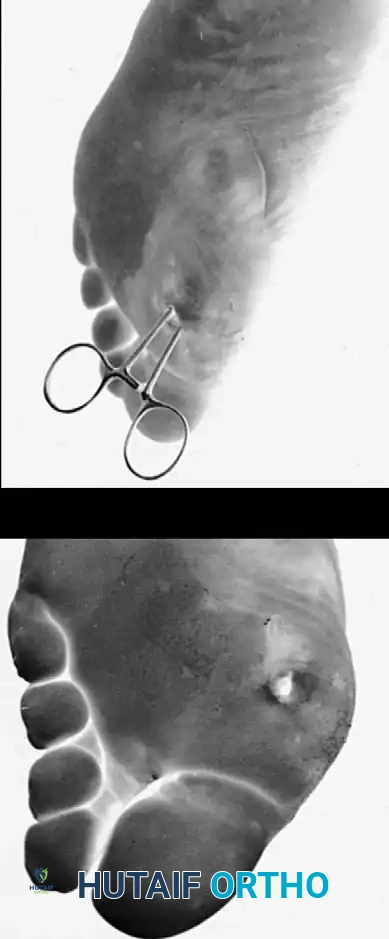

Management of Diabetic Abscesses

Deep space infections in the neuropathic foot can spread rapidly along fascial planes, often with minimal systemic signs of infection due to an impaired neuro-inflammatory response.

Fig. 82-11: Diabetic abscess. (A) Note the subtle discoloration and swelling proximal to the primary ulceration beneath the first metatarsal head, indicating deep tracking of the infection. (B) Intraoperative view demonstrating the remarkable depth of the abscess cavity, requiring extensive surgical exploration and débridement.

Surgical Approach to Deep Abscesses:

1. Positioning: The patient is positioned supine. A thigh tourniquet is applied but inflated only if necessary, as ischemic preconditioning is poor in these patients.

2. Incision: Generous incisions are made, often incorporating the ulcer itself. Plantar incisions should be placed parallel to the weight-bearing axis or in non-weight-bearing zones when possible.

3. Débridement: All necrotic fascia, tendon, and infected bone must be radically excised. "When in doubt, cut it out." The margins of resection must extend to healthy, bleeding tissue.

4. Irrigation: High-volume, low-pressure pulsatile lavage is utilized.

5. Closure: These wounds are never closed primarily. They are packed open or managed with Negative Pressure Wound Therapy (NPWT) to encourage secondary intention healing or to prepare the bed for delayed primary closure or skin grafting.